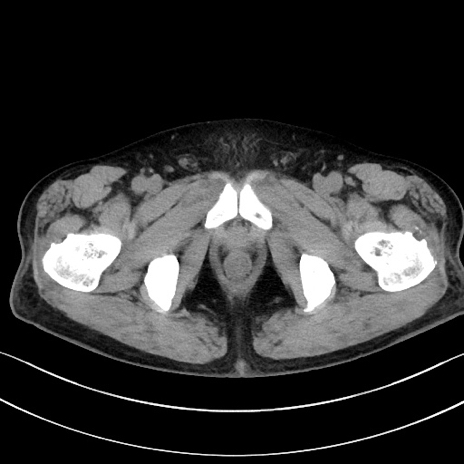

症例15(横断像)

【症例】70歳代男性

【主訴】腹痛

【現病歴】今朝から腹痛あり。全体的に痛い。特に左上の方。排ガスが今日はない。冷や汗が出る。

【既往歴】直腸癌術後

【身体所見】左側腹部〜上腹部に圧痛あり。腹膜刺激症状明らかなではない。軽度反跳痛。左下腹部に術後瘢痕あり。

【データ】WBC 7700、CRP 0.02